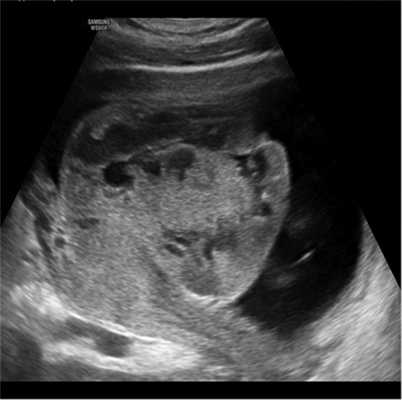

Подгруппу 1С составили 29 беременных с массивными расширениями МВП, т.е. общая площадь структурных изменений плаценты превышала ⅓ от максимального сечения (рис. 5).

Рис. 5. Массивные структурные изменения плаценты в виде расширения МВП.

Среди них у 18 пациенток беременность была первой, у 11 — повторной. У отдельных пациенток беременность была отягощена хроническими соматическими заболеваниями (см. рис. 1): СД 1-го типа — у 5 (17,2%) беременных, ГСД — у 1 (3,4%) беременной, хроническая болезнь почек — в 4 (13,7%) наблюдениях.

Отягощенный акушерский анамнез среди повторнобеременных отмечен в 8 наблюдениях: антенатальная гибель плода произошла в 1 наблюдении, интранатальная гибель — у 1 пациентки, невынашивание беременности — прерывание в I триместре — 3 наблюдения, отслойка плаценты в конце II—начале III триместра — 3 наблюдения, т.е. в 72,7% исход предыдущей беременности был неблагоприятный.

Данная беременность протекала с осложнениями: активация ВПГ-инфекции — в 1 наблюдении, СЗРП I степени — в 1 наблюдении, СЗРП II степени — у 2 пациенток, СЗРП III степени — у 3, выявлены критические показатели плодового кровотока при первом обращении — у 2 беременных, антенатальная гибель плода — у 1, массивный субхориальный тромбоз — у 1, диабетическая фетопатия — у 2 пациенток. Таким образом, в 29,1% наблюдений при первом посещении выявлены некомпенсированные тяжелые осложнения во время данной беременности, препятствующие рождению доношенного здорового новорожденного.

Из группы 1С 9 беременных не были обследованы на полиморфизм генов гемостаза. Среди обследованных не выявлено мутаций у 2 (10%) беременных, выявлены мутации у 18 (90%) беременных, среди них мутация Leiden — в 1 (0,5%) наблюдении, сочетанные — в 17 (89,5%) наблюдениях. Чувствительность признака составила 90%, доля ложноположительных предположений — 10%.